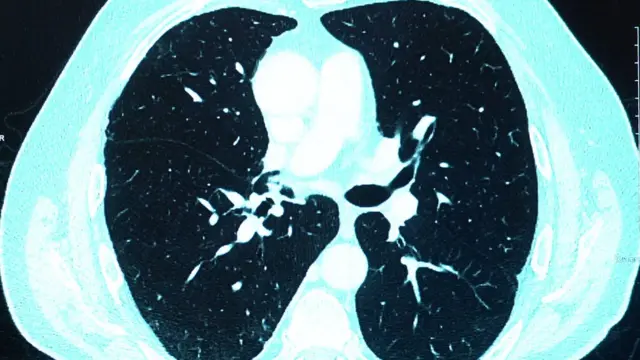

ফুসফুসে আস্তরণ

হাসপাতালে সিটি স্ক্যানে দেখা গেছে করোনাভাইরাসে আক্রান্ত হবার পর তার দুটি ফুসফুসের ওপরই একটা সাদা কুয়াশার আস্তরণ তৈরি হয়েছে- অনেকটা ভাঙা কাঁচের মত দেখতে। চিকিৎসকরা বলছেন এটা করোনাভাইরাস আক্রমণের একটা বৈশিষ্ট্য।

করোনাভাইরাসে গুরুতরভাবে আক্রান্ত হলে শরীরের প্রতিরোধী ব্যবস্থা যখন অতিমাত্রায় সক্রিয় হয়ে ওঠে, তখন এর ফলে প্রচুর শ্লেষ্মা, জলীয় পদার্থ এবং কোষ তৈরি হয়, যা ফুসফুসে যে বাতাস চলাচলের থলিগুলো আছে যাকে অ্যালভিওলি বলা হয়, সেগুলোকে ভর্তি করে ফেলে। এটা যখন হয়, তখন নিউমোনিয়া দেখা দেয় এবং সাহায্য ছাড়া মানুষের পক্ষে নিঃশ্বাস নেয়া সম্ভব হয় না।

আক্রান্ত হবার ছয় সপ্তাহ পর নেয়া মি. ম্যাকহিউয়ের এক্স-রে-তে দেখা গেছে তার ফুসফুসের ওপর একটা সাদা ছায়ার মত স্তর তৈরি হয়েছে যেটাকে ডাক্তাররা বলছেন পালমোনারি ফাইব্রোসিস বা ফুসফুসে ক্ষত সৃষ্টির প্রাথমিক লক্ষণ।

ব্রিটিশ সোসাইটি অফ থোরাসিক ইমেজিংএর একজন সদস্য এবং রয়াল কলেজ অফ রেডিওলজিস্টের উপদেষ্টা ড. স্যাম হেয়ার বলছেন, "সাধারণত এধরনের ভাইরাস সংক্রমণের পর ছয় সপ্তাহ হয়ে গেলে ফুসফুসের অবস্থা আবার আগের জায়গায় ফিরে যাবার কথা- অন্তত চিকিৎসকরা সেটাই আশা করেন। কিন্তু এক্ষেত্রে সেটা হয়নি এবং সেজন্যই এটা উদ্বেগের কারণ।"